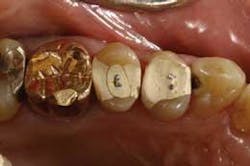

From the very first three units I cemented, I knew there was something special about the Wol-Ceram system. These were the first all-ceramic crowns I had ever inserted that felt like PFMs as they slid down into place. There is nothing quite so reassuring as being able to feel the mechanical retention of a crown as it moves down the prep.